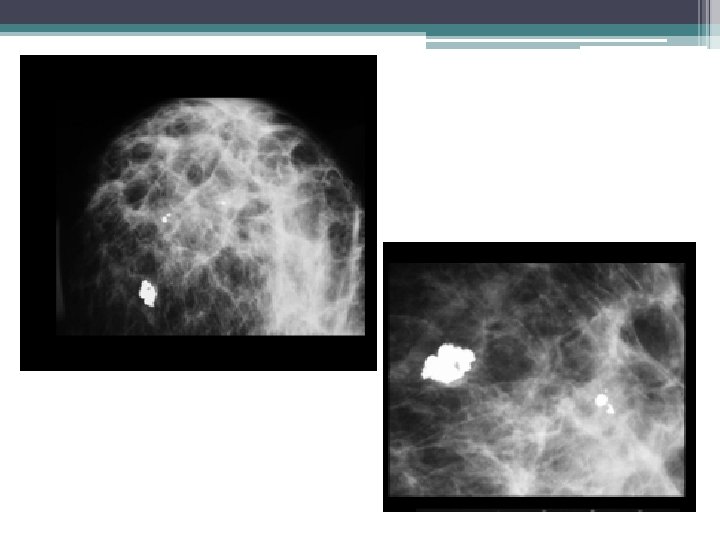

ADENOFIBROME • MAMMOGRAPHIE: ▫ ▫ Opacité dense, ronde ou ovalaire, bien limitée Contours nets, polylobés halo radio transparent Calcifications �typiques: grossières, confluentes, (pop corn) �atypiques: punctiformes ou linéaire

▫ micro calcifications : �FORME: ▫ classification de Le Gal �REPARTITION: ▫ Diffuses, éparses: Bénin ▫ Canalaires, segmentaires, Amas ( >5): Malin ▫ Les désorganisations architecturales : �Perturbation de l’architecture du sein, sans masse identifiable. ▫ Les signes associés : �rétraction cutanée/ mamelonnaire, �épaississement cutané (focal ou diffus) �adénopathies axillaires.

Classification de Le Gal des microcalcifications: 36% 0% 22% 52% 90%